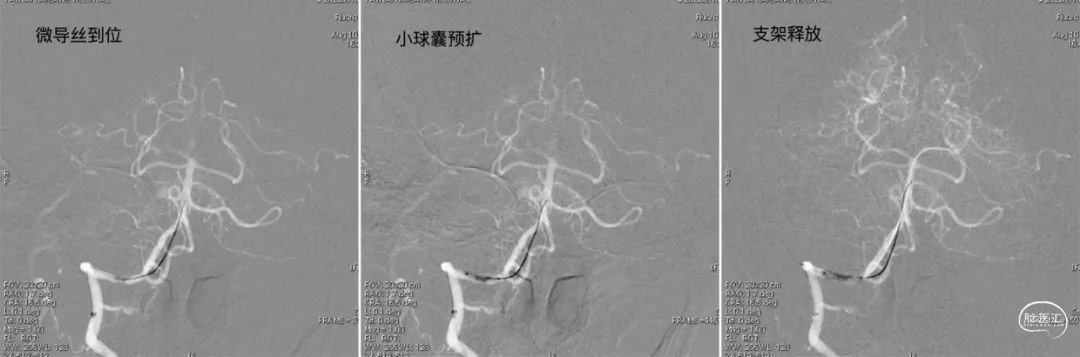

治疗中影像

病变情况分析:右桡动脉穿刺,置6F桡动脉鞘管,5F多功能导管在泥鳅导丝辅助下脑血管造影提示:右椎动脉V4段重度狭窄(约90%)。

泥鳅导丝携5F 115cm颅内支撑导管,至右椎动脉V2段。

在颅内支撑导管支撑下,将0.014'' 300cm微导丝,通过狭窄节段将其放置在基底动脉中段。将2.0mm*10mm球囊打起预扩狭窄部位,然后更换赛诺神畅 颅内药物洗脱支架NOVA DES® 2.5*10mm延微导丝顺利通过狭窄节段,再次造影见定位准确,缓慢扩张球囊释放支架。

术后影像

术后即刻影像及患者术后情况:

造影见狭窄位置狭窄解除,支架贴壁良好,后循环各分支动脉显影良好。术后次日患者行走不稳情况明显改善,术后1月随访患者行走如常,未再发头晕。